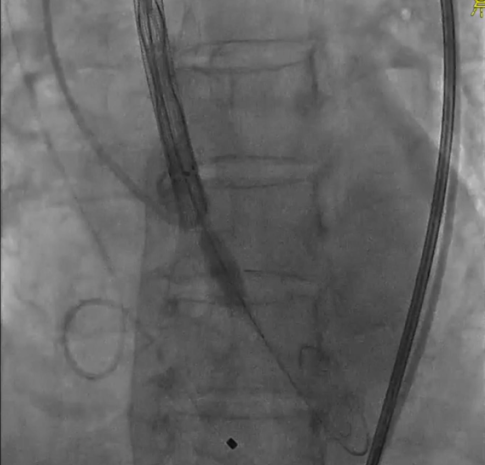

TaurusEliteAV23第一次释放,预释放;

初始定位;

近左右重合位,瓣下1mm释放,释放过程中瓣膜下滑瓣膜展开至工作位;

左冠切线位评估,瓣架底边对齐,左冠显影良好,大弯侧深度约8mm,同轴性较差,瓣膜几无压缩,决定回收;